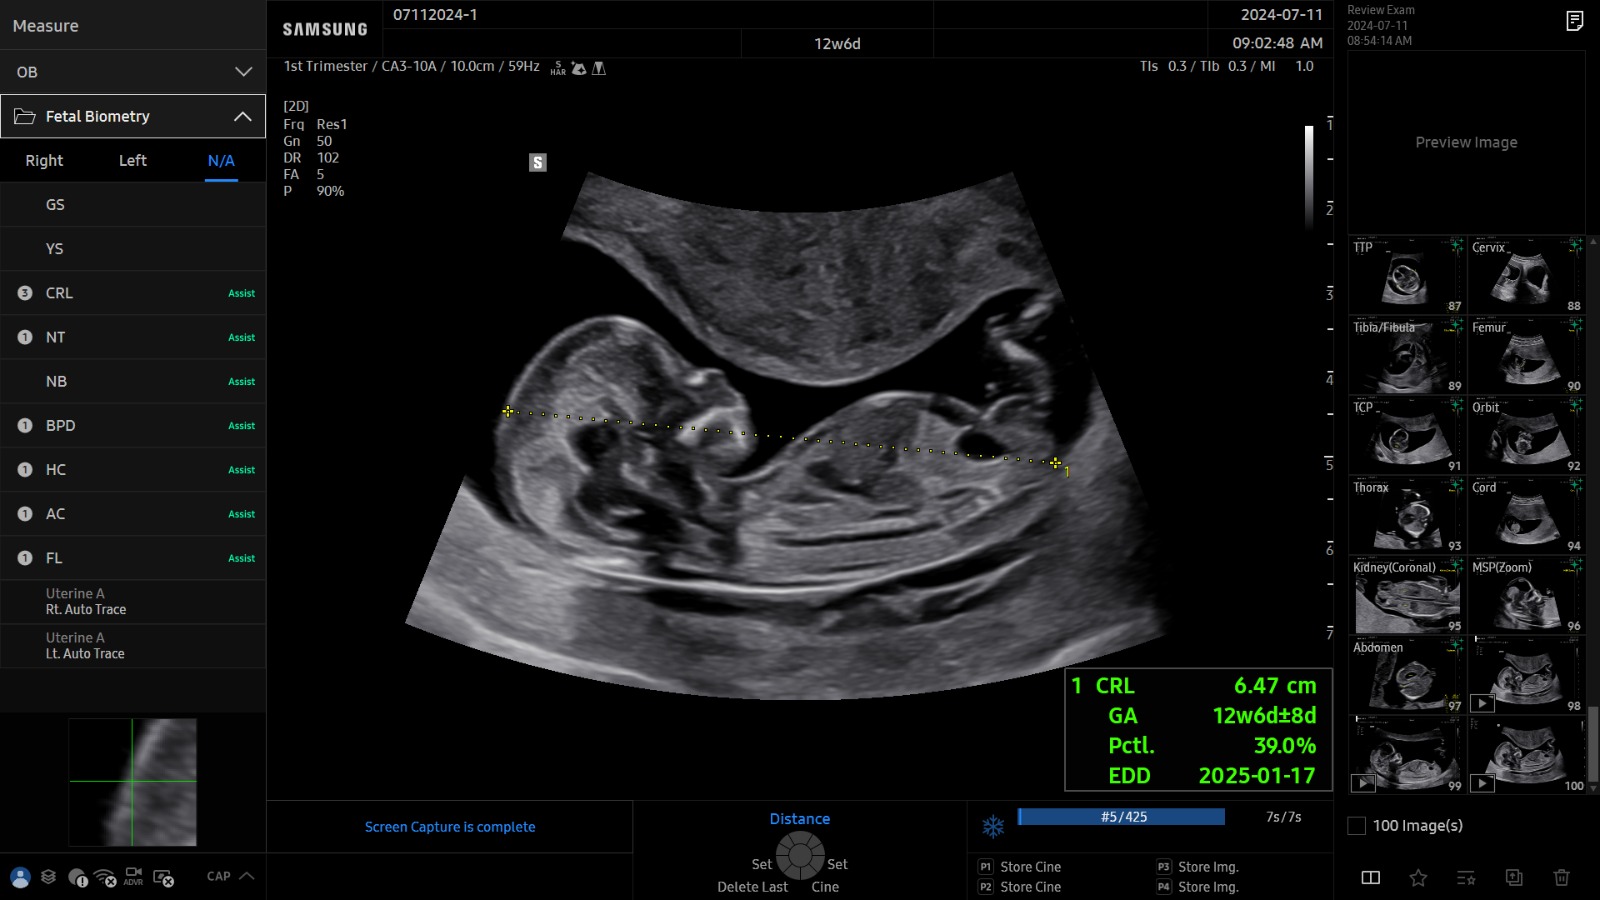

BiometryAssist™ est une technologie de mesure de biométries fœtales automatique qui permet à l’utilisateur de gagner en efficacité et en productivité.